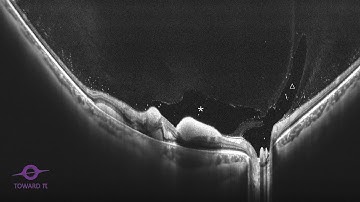

Widefield OCTA Capture time of BMizar 400KHz SS-OCTA system from TowardPi